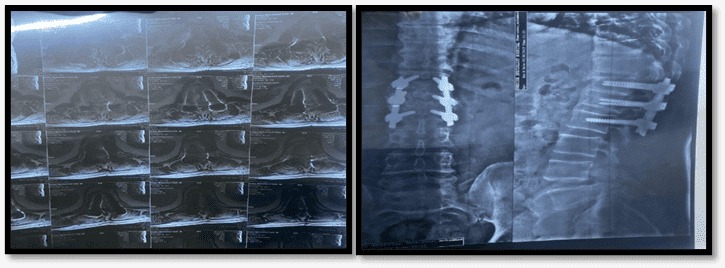

لێوی خوارەوەی دەلەرزێت کاتێک بە دڵتەنگی سەری دەهەژێنێت. "پشکنیینەکان دەریانخست کە بڕبڕەی پێنجەم و شەشەمی پشتم پارچە پارچە بووە، زیانەکانیش گەیشتوونەتە حەبلی شەوکیم" یونس بۆ ماوەی حەوت مانگ لە جێگادا بووە پێش ئەوەی بتوانێت بە بەکارهێنانی دارشەق بڕوات، هەوڵدەدات خۆی لەگەڵ کەمئەندامییەکی هەمیشەیی بگونجێنێت کە پێویستە بۆرییەکی لاستیکی بەکاربهێنێت بۆ میزکردن.

وێنەی تیشکی بڕبڕەکانی پشتی (یونس)ی کرێکار